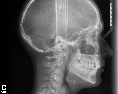

Недавно задумалась об установке брекет-системы, выбрала клинику, сходила на консультацию. Врач сказала, что у меня большая скученность зубов, зубы неправильно смыкаются, вследствие чего могут быть в будущем проблемы с челюстями, так же развивается пародонтоз из-за кривого развития зубов. Врач посоветовала мне самолигирующиеся брекеты, но они мне не по карману, я рассчитывала ставить обычные керамические брекеты. Скажите, если пациент выбирает брекет-систему, исходя из своих финансовых возможностей, то любая, выбранная система будет положительна для лечения прикуса?

Уважаемая Ирина, пациент не выбирает брекет-систему и не ставит диагнозы. Но в вашем случае можно абсолютно спокойно установить керамические системы, отличаются они от самолигирующих только тем, что обычные лигатурные керамические будут регулироваться на приеме у врача раз в две недели.